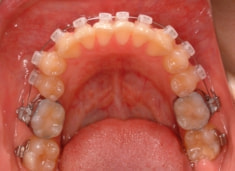

治療後(1年9ヶ月後)